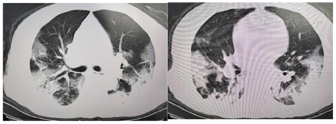

入院检查:血常规:白细胞4.9×109/L,中性粒细胞比值88.1%,淋巴细胞比值7.3%;生化检查:钾3.2mmol/l,钠133.1mmol/l,白蛋白28.4g/l,C反应蛋白23.06mg/l,降钙素原0.12ng/ml;血气分析:PH 7.44,PaCO2 39mmHg,PaO2 52mmHg,Lac 1.8mmol/L,BE 2.3mmol/L;核酸检测:咽拭子荧光RT-PCR检测新型冠状病毒核酸阳性,鼻拭子荧光RT-PCR检测新型冠状病毒核酸阳性。肺部CT示双肺中下叶外带多发斑片状磨玻璃影(图1)。入院诊断:1、新型冠状病毒肺炎(重型)急性呼吸衰竭(I型) 2、高血压病2级(很高危) 3、Ⅱ型糖尿病4、冠心病5、低钠血症6、低钾血症。患者入院后给予洛匹那韦、利托那韦、利巴韦林抗病毒,莫西沙星抗菌,丙种球蛋白、胸腺法新免疫调节[2]及对症等治疗。入院7日后(2020年2月26日)患者呼吸困难呈进行性加重,经皮指脉氧饱和度降至78%,先后给予经鼻高流量、无创支持通气后效果欠佳,行床旁气管插管及有创机械通气支持,诊断新型冠状病毒肺炎(危重型)[1],转入负压重症隔离病房继续治疗。

| 2020你啊3月10日 | 1.参与配合能力配合(S5Q=5) 2.心血管呼吸系统复合能力基础评估通过3.MRCsum>36分4.鼻胃管、尿管已拔除5.胸部CT见双肺外带渗出较前明显吸收 | 2级 | 1.协助坐于床边2.主动关节活动(伸屈膝及屈髋运动、上下肢弹力带力量及抗阻训练等)3.呼吸功能锻炼(呼吸练习、放松练习、拉伸柔韧性练习、排痰练习、呼吸训练器练习等) |